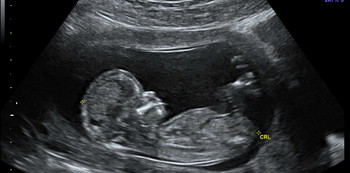

Photo from: wikimedia commons